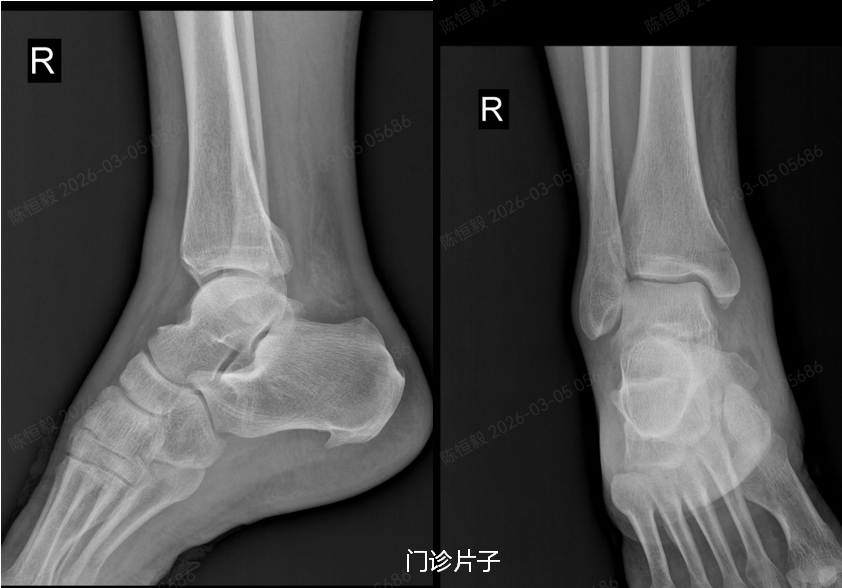

在成人ai 拍 X 光片后未见明显骨裂,王大爷更是觉得无需治疗,准备回家自行休养。

但接诊的足踝外科主任杨建义查看片子并仔细为其体格检查后,发现了异常,当即告知王大爷,其下胫腓部位大概率存在损伤,建议住院做进一步详细检查,排除隐匿性问题。

王大爷听从建议住院后,经完善体格检查及 CT 检查,最终确诊为复杂的 Maisonneuve 骨折:不仅存在下胫腓分离,还合并前踝 Chapute 结节撕脱骨折、后踝骨折、内踝骨折,同时伴有腓骨高位骨折。

普通 X 光片仅能判断是否存在明显骨折、脱位,对于下胫腓联合损伤、微小骨折、软骨损伤,以及 Maisonneuve 骨折涉及的腓骨高位骨折等隐匿性损伤,很难清晰显示。